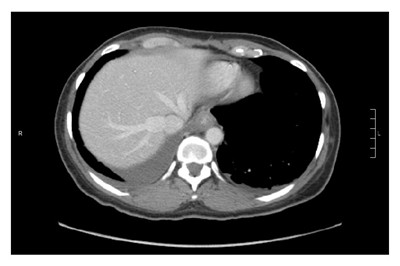

病例报告 一名41岁的非裔男性,无吸烟史,被诊断为IV期非小细胞肺癌(NSCLC,腺癌),右肺结节;同侧胸腔积液;纵隔、颈部和腹膜后淋巴结广泛受累。诊断时脑磁共振成像的结果转移阴性。积液细胞学样本下一代测序显示cis L858R和K860I EGFR突变。 患者开始接受厄洛替尼(每日一次150mg)治疗,对治疗有部分反应。接受厄洛替尼治疗20个月后,对复发性积液的分析显示L858R和K860I突变及获得性T790M突变。患者参加1/2期临床试验,接受第三代EGFR抑制剂rociletinib(500 mg)治疗,表现出对治疗的部分反应约5个月,后中枢神经系统(CNS)进展。中枢神经系统疾病接受立体定向放射治疗,患者继续接受研究治疗。治疗13个月后,发生腹膜进展。停用Rociletinib并开始使用卡铂和培美曲塞治疗,而后接受培美曲塞维持治疗。 治疗7个月后,最佳反应为疾病稳定,患者血清癌胚抗原(CEA)水平上升,并且观察到新的CNS病变。他再次接受了立体定向放射治疗,厄洛替尼(每日一次150mg)+培美曲塞治疗一个周期后,正电子发射断层扫描/计算机断层扫描显示,纵隔淋巴结和腹膜再次进展。虽然当时没有再次进行分子检测,但鉴于之前T790M阳性,患者从厄洛替尼转而接受另一种第三代EGFR抑制剂奥希替尼(每日80mg)治疗。在治疗的前2个月,患者的CEA水平从553.3 ng/mL(正常范围0-3 ng/mL)降至257.0 ng/mL,先前所有正电子发射断层扫描阳性病变吸收均降低。然而,在治疗约6个月后,患者因腹痛和腹胀而住院。影像学检查显示腹膜炎伴腹膜增厚,CEA水平显著升高至452.8 ng/mL。 大网膜活检显示L858R和K860I基线EGFR突变,下一代测序未检测到T790M,FISH检测出中等水平MET扩增,平均MET细胞比率为29.98,MET-CEP7比例为3.67。患者开始接受奥希替尼(每日一次80mg)+MET抑制剂克唑替尼(200mg,每日两次)治疗。克唑替尼(Crizotinib、Crizonix、赛可瑞、Xalkori)是一种口服多激酶抑制剂。 联合治疗使患者症状快速改善,没有报告副作用。在开始治疗后3周内,患者的CEA水平显著下降。治疗2个月和4个月后影像学检查显示腹水和腹膜增厚几乎完全消退。尽管影像学检查结果改善,治疗4个月后,患者的CEA水平从最低点50ng/mL增加至173ng/mL,一周后升至230 ng/mL。因CEA水平的升高,将克唑替尼剂量逐渐增加至250mg每日两次;2个月内患者的CEA水平降低至183ng/mL,后进一步降至164 ng/mL。全剂量克唑替尼+奥希替尼治疗与2个月后2级间歇性疲劳缓慢发展相关,耐受性没有其他变化。6个月时影像学检查显示病情稳定。联合治疗3个月和6个月后脑磁共振成像扫描结果持续稳定。 Scheffler等最近报告一例EGFR-突变NSCLC病例,其在初始EGFR TKI治疗后在一些病变中出现获得性MET扩增,对厄洛替尼+克唑替尼组合有反应,同时其他部位进展,后在进一步分析中显示携带T790M。患者转为接受第三代EGFR抑制剂单药治疗,结果仅T790M病灶有反应,之前显示为MET扩增的部位进展。随着第三代EGFR抑制剂以及克唑替尼等MET抑制剂的出现,现在可以在常规实践中对T790M和MET进行双重抑制。 对于本文这一病例,抑制T790M后耐药后MET扩增成为主要作用机制,用奥希替尼(每日一次80mg)+MET抑制剂克唑替尼(200mg,每日两次)组合有效靶向该突变。值得注意的是,较高剂量的克唑替尼可能与更有效地抑制MET阳性疾病有关,因为接受200 mg克唑替尼治疗4个月后剂量递增至250 mg逆转了CEA水平升高的趋势。其他对奥希替尼等第三代EGFR抑制剂耐药的机制包括EGFR C797S突变,BRAF V600E突变,erb-b2受体酪氨酸激酶2基因(HER2)扩增和小细胞转换等。奥希替尼+克唑替尼治疗或甚至预防EGFR突变NSCLC中多种获得性耐药机制的潜力应进一步研究。正在进行相关前瞻性临床试验。 本内容为医伴旅版权所有,转载请注明出处。 医伴旅:寻找优质医疗资源,伴您走上康复之旅